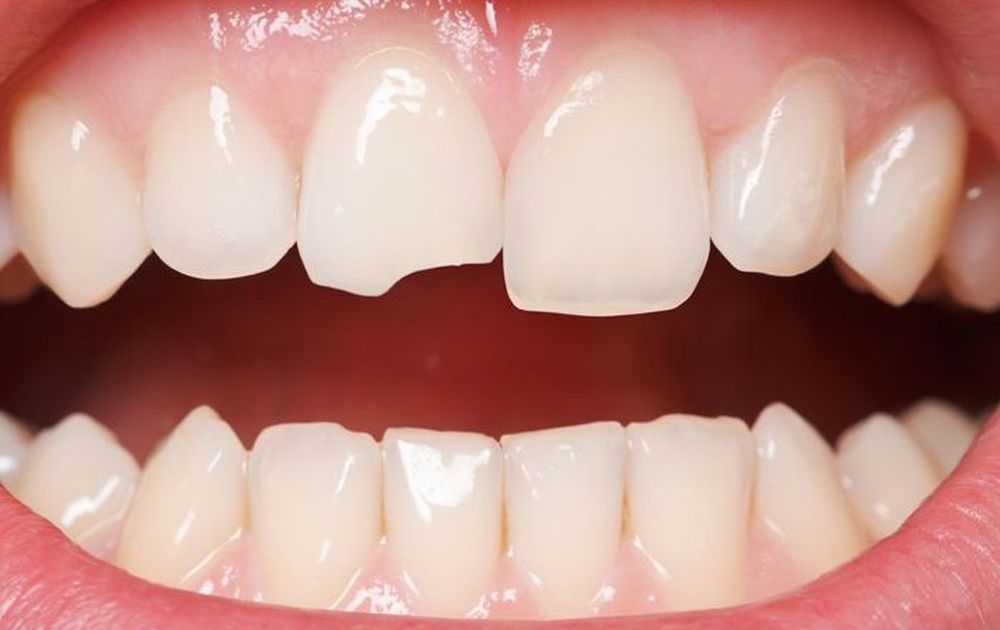

Răng cửa bị mẻ thường là kết quả của các chấn thương răng phổ biến trong cuộc sống hàng ngày. Nguyên nhân của vấn đề này rất đa dạng, từ việc té ngã, chấn thương, đến sử dụng lực cắn quá mạnh hoặc thiếu canxi. Việc cắn nhai mạnh có thể gây mẻ răng cửa bởi sự yếu đuối của các liên kết mô răng. Ngoài ra, những bệnh lý nha khoa như viêm tủy cũng có thể làm yếu đi răng và dẫn đến tình trạng này.

Mẻ răng cửa thường xuất hiện ở vùng mà bạn áp dụng lực cắn mạnh nhất, thường là cạnh răng cắn. Điều này là dễ nhận biết vì răng cửa thường nằm ở vị trí trung tâm.

Mẻ răng cửa không chỉ gây mất thẩm mỹ cho hàm răng mà còn ảnh hưởng đến tự tin khi giao tiếp. Nó cũng làm cho việc ăn uống trở nên khó khăn và làm mất đi cảm giác ngon miệng khi ăn. Vì vậy, việc khắc phục tình trạng này cần được thực hiện sớm để tránh các vấn đề tiềm ẩn.